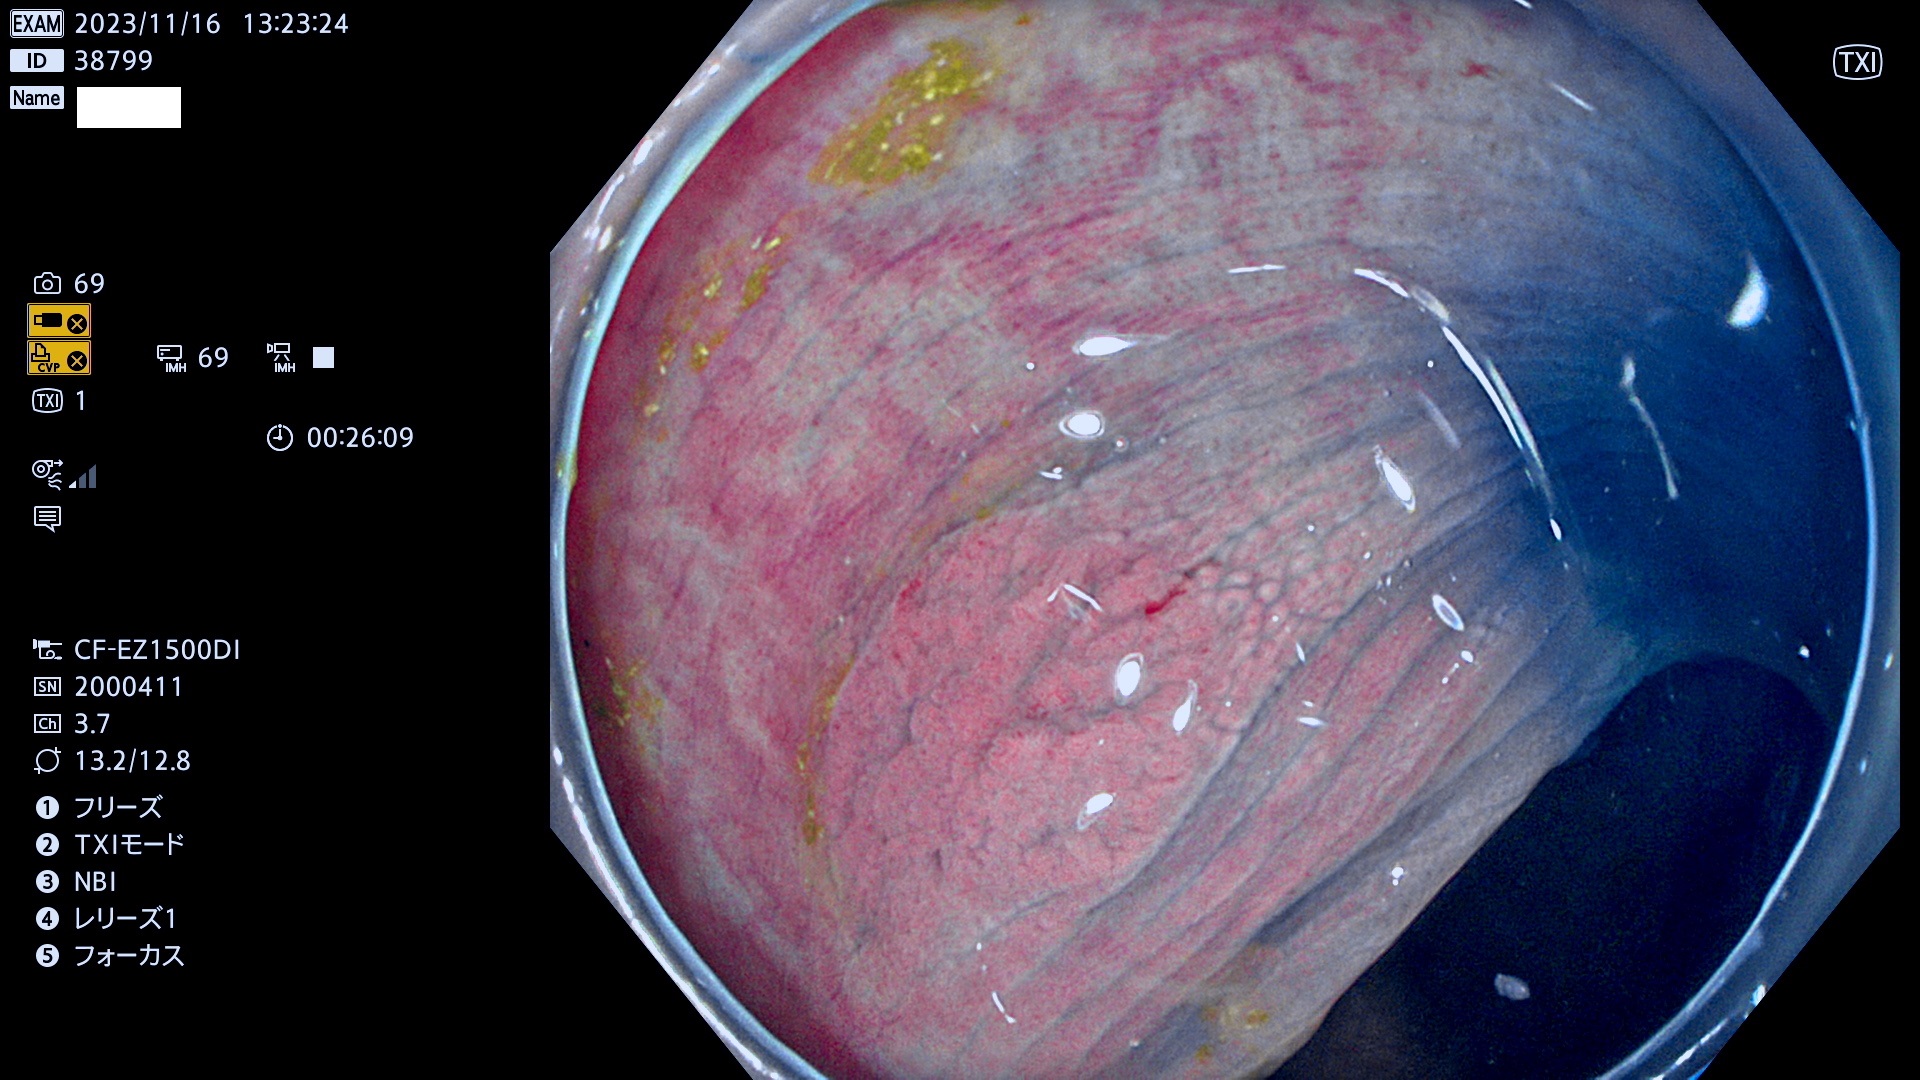

今週のUb、Uc型腺腫

表面型腺腫(Flat Adenoma)の中で、完全に平坦な物をUb、陥凹している物をUcと呼びます。平坦隆起型(Ua)よりも、発見が難しく危険な病変です。このタイプは「内視鏡後・大腸癌の重要犯人」であり、この発見率は「腺腫発見率」よりも、重要な意味があります。

毎週の検査(木・金・土・日)に発見されたUb、Uc型・腺腫を、その週の日曜の夜にUPし1週間、提示します。

抽出の対象期間 2023年11月16日(木)〜11月20(日)の5日間(60件の検査)11件